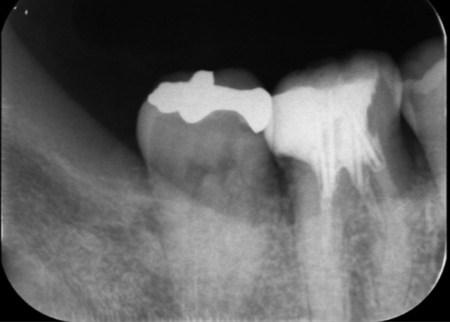

詳しく検査した結果、右上の小臼歯の周囲には膿の袋ができており、痛みや違和感の原因になっていると考えられました。

これは歯の神経が通る根管内の感染と、歯を支える歯ぐきや骨といった歯周組織の炎症が同時に起きている「エンドペリオ病変」と呼ばれる状態です。

レントゲンを撮影したところ、歯の周囲の骨が溶けて歯ぐきの深い部分にまで歯石が付着していることが確認できました。

まず、右上奥歯の精密根管治療を行いました。

マイクロスコープ(歯科用顕微鏡)を用いて根管内を拡大視野で確認しながら、感染した組織を丁寧に除去しました。その後、再感染を防ぐため根管内に薬剤を充填しています。